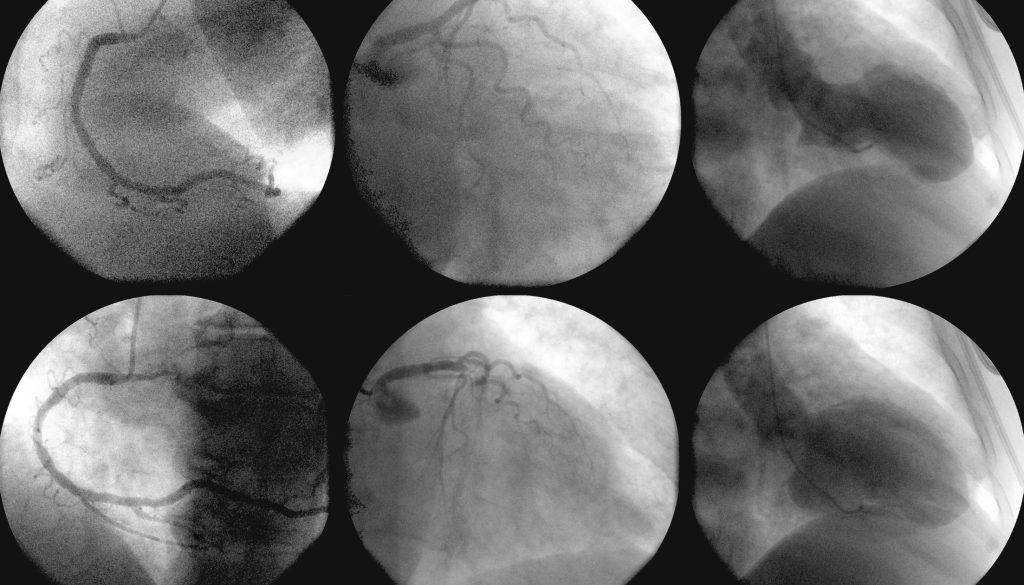

3. **تصوير الشرايين التاجية:**

يتم حقن صبغة خاصة لرؤية الأوعية الدموية في الصور الإشعاعية.

يتم حقن صبغة لتوضيح الأوعية الدموية في الأشعة السينية.